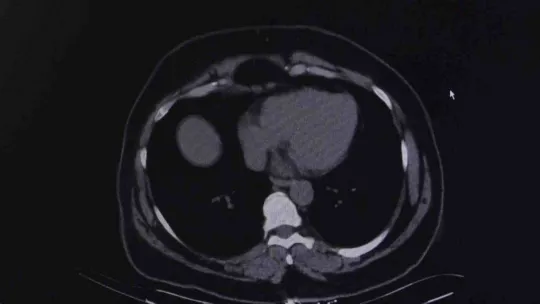

Havaların soğumasıyla birlikte üst solunum yolu hastalıklarında artış yaşanıyor. Bu durumun özellikle KOAH (Kronik Obstrüktif Akciğer Hastalığı) ve solunum rahatsızlığı bulunan vatandaşlar için farklı etkiler oluşturduğuna dikkat çekiliyor. Yedikule Göğüs Hastalıkları ve Göğüs Cerrahisi Eğitim Araştırma Hastanesi’nden Göğüs Hastalıkları Uzmanı Doç. Dr. Seda Tural Önür de hastalığa ilişkin açıklamalarda bulundu. Doç. Dr. Seda Tural Önür, kış aylarında atakların arttığına dikkat çekerken vatandaşların şikayetlerini sigaraya bağlayarak doktora geç başvurduğuna vurgu yaptı.

KOAH’ın belirtilerine ilişkin bilgiler veren Göğüs Hastalıkları Uzmanı Doç. Dr. Seda Tural Önür, “Akciğerlerden gelen temiz hava vücuda ulaşamadığı zaman nefes darlığı şikayeti en belirgin bulgusudur. Bu hastalarda öksürük, balgam çıkarma, yol yürürken nefes darlığıyla kesilme, egzersiz yaparken kesilme çok belirgin semptomlardır. Daha çok 40 yaşın üzerinde görebildiğimiz bir hastalık ama sigara kullanımıyla beraber artık erken KOAH ya da pre KOAH dediğimiz tanımlarda genç yaşta önümüze gelmekte. 40 yaşın üzerinde yaklaşık olarak yüzde 20 sıklığında görülebilen bir hastalık, yapılan çalışmalarda 10 erkekten bir tanesinde görülen bir hastalık olarak tanımlanırken kadınlarda sigara kullanımının artmasıyla beraber bu rakamda erkekleri yakalamış durumda. Hiç tütün kullanmayan kişilerde de görülme sıklığı yüzde 10 civarında olabilmektedir. Yapılan meslekler bu hastalığın oluşabilmesi için bir neden olabilmektedir. Gizli kalmış bir hasta olabilirsiniz, sigara kullanıyorsanız, nefes darlığı ve balgam şikayetiniz varsa bunu sadece sigaraya adlandırmadan mutlaka bir hekime başvurmak lazım KOAH hastası olabilirsiniz. Tütün ve tütün ürünlerinin kullanımı KOAH gelişiminde önemli bir risk faktörü. Sigara içmeyen bir kişi günde 8 saat, 5 günlük bir mesaisini 5 yıl tamamladığında pasif sigara dumanına maruz ise yüzde 50 oranında KOAH geliştirme ihtimali var, sigara içmemiş olmasına rağmen bu ciddi bir oran. Çimento üretimi, tekstil, maden işçiliği, tarımla uğraşanlar, metal sektöründe çalışanlar, fırıncılık, marangozluk işleriyle uğraşan kişilerin de sigara kullanmadan bağımsız olarak mesleksel olarak KOAH gelişimine yatkınlıkları olabiliyor” dedi.

KOAH’ın tanı ve tedavisinin konulmaması durumunda ölüme neden olduğuna dikkat çeken Doç. Dr. Seda Tural Önür, “En sık 3. ölüm nedeni olarak KOAH tanımlamıştır. Dünyada ölümlerin yüzde 5 buçuğundan KOAH sorumludur. Bu hastalık ataklarla seyreden bir hastalıktır her atak hastalığın daha da ilerlemesine, bu sebeple hastalığın ataklarının da takiplerle, kontrol altına alınması ve önlenmesi son derece önemlidir. İlerleyici bir hastalık olduğu gibi önlenebilir bir hastalıktır. Özellikle kış aylarında daha sık olarak bu hastalığın tanısının konduğunu, ataklarla karşımıza gelen hastalarla beraber görebiliyoruz. Ev içi ve dış hava kirliliğinin kullanılan yakıtlarla beraber artması özellikle kış dönemlerinde atakların artmasına ve hastaların daha çok hastaneye başvurmasına ve ölümle seyreden sonuçlara neden olabilmektedir. Yine gribal enfeksiyonlar, kış aylarında üst hava yolları enfeksiyonları atak sıklığını arttırdığı için bu hastalarda ciddi seyredebilmektedir. Dünya Sağlık Örgütü de o yüzden bu hastalarda grip ve zatürre aşısının mutlaka yapılmasını ve enfeksiyonlardan bu hastaların öncelikli olarak korunması gerektiğini, atakları koruduğundan dolayı mutlaka önermektedir. Şikayetlerini sigara kullanımına bağlayarak sağlık kuruluşlarına daha geç başvurabiliyorlar. İlerleyen dönemlerinde de hastalık solunum yetmezliği tablosuyla beraber çeşitli oksijen cihazlarına bağlı kalma durumları dahi söz konusu olabiliyor” ifadelerini kullandı.